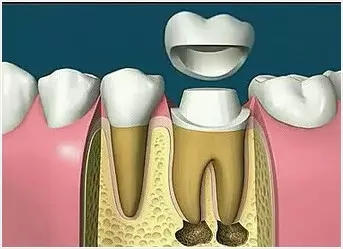

8、完成牙體修復(fù)

X線片顯示根管充填完好,行暫時或永久牙體修復(fù),帶上牙冠,保護患牙。至此根管治療才可算完成,同時根管治療后還需復(fù)診,一般周期可為3個月、半年、1年、2年或更長。